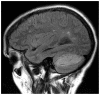

We report the case of a patient with pre-existing multiple sclerosis, who presented with horizontal diplopia, and a prior episode of progressive ataxia and dizziness lasting one week. While initially attributed to multiple sclerosis, subsequent imaging demonstrated a concurrent left cerebellar gangliocytoma, also known as Lhermitte-Duclos disease.